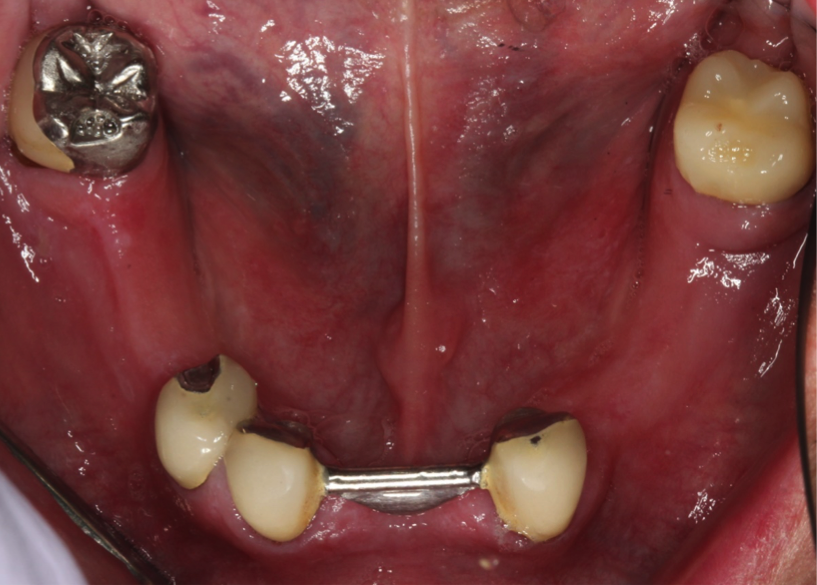

Fixed Implant Bridge

This is what we can do for you! This patient came to us with a few teeth that had crowns that were in bad shape and failing. We placed several implants in his bottom jaw and made him an implant bridge that restored all his teeth. Can you see the difference in how his teeth look?. We also had to fabricate him some gum tissue to make up for the amount of bone and gum he had previously lost.